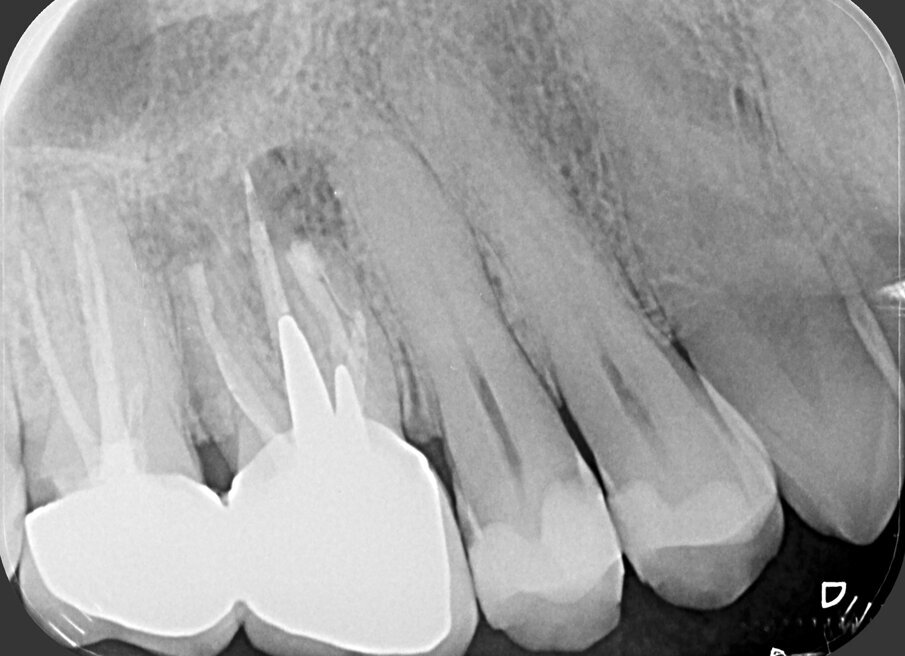

Fig. 2a - Radiografia preoperatoria del secondo molare superiore di sinistra. La paziente lamenta dolore alla masticazione su questo dente, trattato endodonticamente pochi mesi prima. La stessa viene indirizzata con la specifica richiesta di eseguire la terapia chirurgica e di non aprire una cavità d’accesso, allo scopo di non sciupare la “nuova” corona ceramica da poco cementata.

Fig. 2b - Una piccola lesione è evidente all’apice della radice mesiovestibolare.